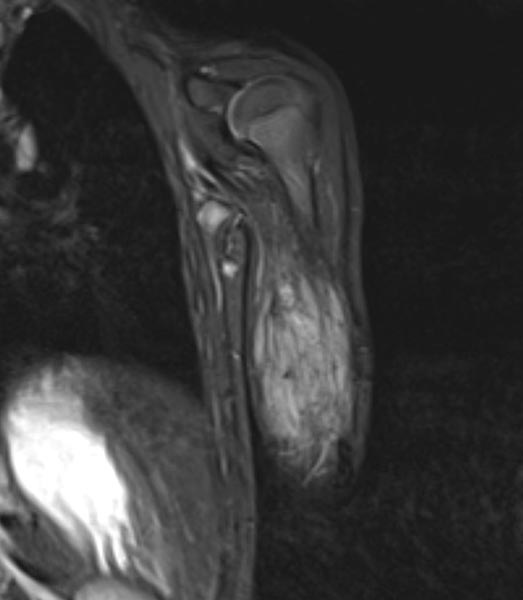

To further confirm the differential diagnosis, the child also underwent MRI, shown here in a coronal, T2-weighted, fat-suppressed STIR sequence. The tumor is highly hyperintense (white) and sharply demarcated from surrounding tissue. It penetrates all tissue planes and centrally contains signal-free areas, so-called flow voids, as a sign of strong arterial perfusion.